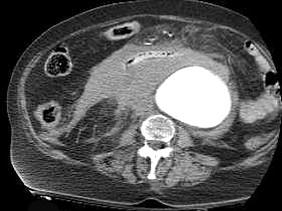

问题 关于腹主动脉瘤,下列哪项是正确的 ( )

选项 A、外科手术是根治腹主动脉瘤的唯一方法 B、CT能够更准确地显示瘤体的三维形态体征 C、腹主动脉瘤病人出现腹痛或腰背痛时意味着动脉瘤破裂 D、MRI在造影剂的帮助下可以充分显示瘤体的大小 E、直径2cm以上的动脉瘤可以用超声多普勒检查出来

答案 C